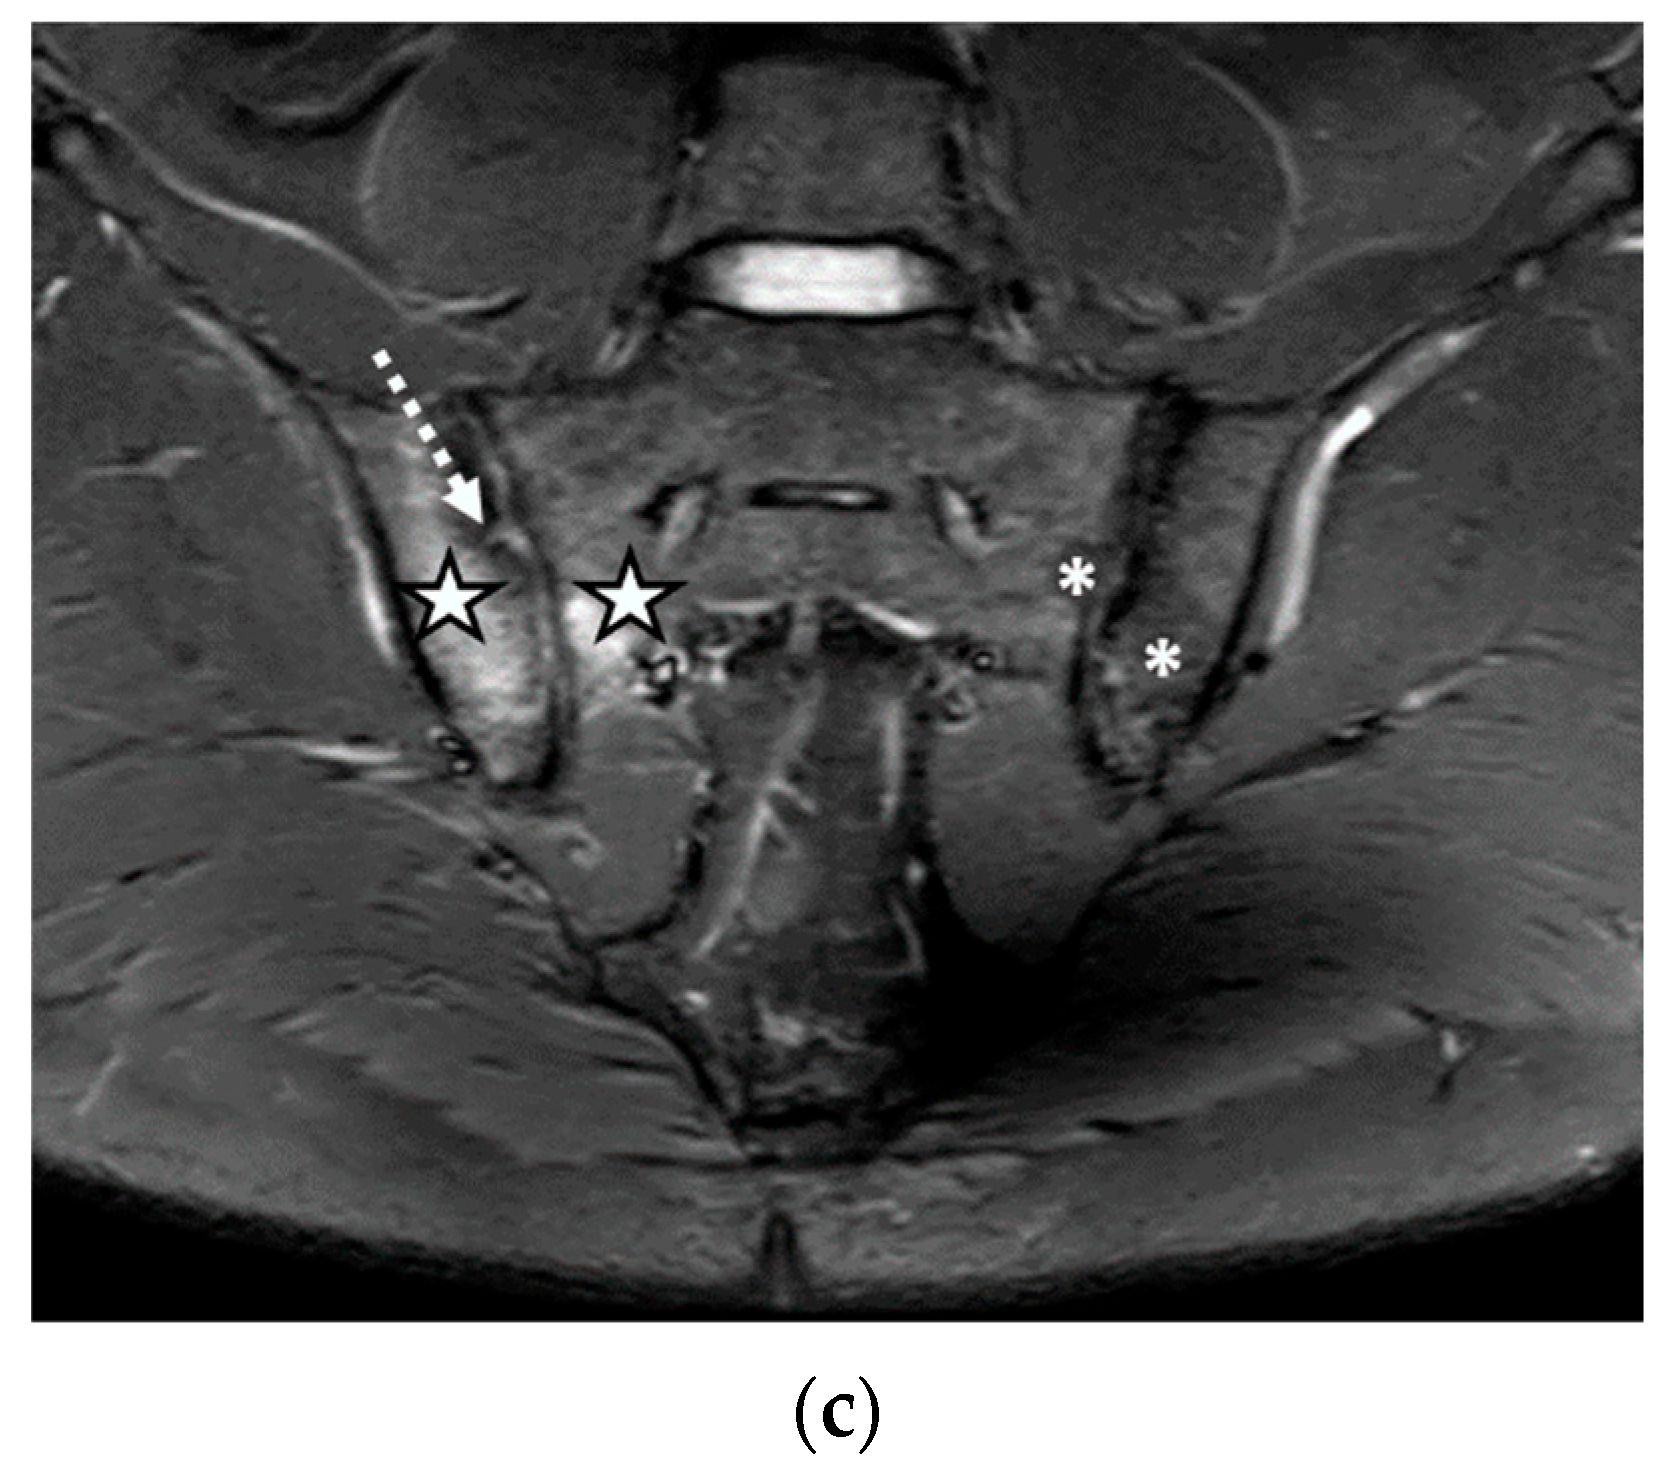

We evaluated 68 sacroiliac joints. The prevalence of MRI-detected abnormalities is presented in Table 2. The results of the SR were considered as the reference data. Inflammatory and structural changes were detected on the MRI sequences of the sacroiliac joints. The most frequently encountered inflammatory change, both on the left and right sacroiliac joint, was the presence of bone marrow edema (44.11–58.82%), followed by enthesitis (17.64–26.47%) and synovitis (11.76–17.64%). Regarding structural changes, the most prominent was subchondral sclerosis (50–59.37%), followed by erosions (35.29–41.17%), joint space narrowing (38.23%), fat metaplasia (17.64–23.25%), and backfill (11.76–20.58%) (Figure 1, Figure 2 and Figure 3).

Figure 3.

The MRI aspect of the sacroiliac joints included pseudo-widening of both sacroiliac joints, with marked bone marrow edema (star) of both the sacrum and the right iliac bone, in the proximity of the ipsilateral sacroiliac joint space, right iliac bone erosions (discontinuous arrow), bilateral subchondral sclerosis (continuous arrow), and fat metaplasia (asterisk), affecting the left iliac bone, and the left part of the sacrum and backfill (arrowhead) of the left sacroiliac joint space: (a) T1-weighted sequence; (b) T2-weighted sequence (without fat suppression); (c) STIR sequence.